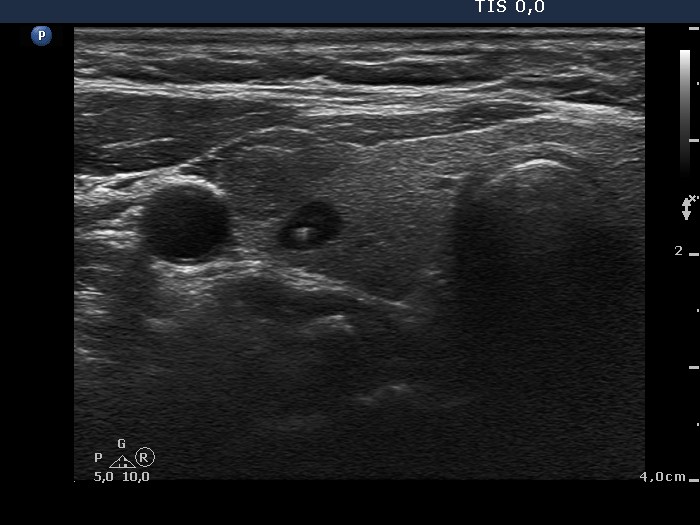

Benign hyperplastic nodule (histological diagnosis) - case 2 |

Hashimoto's thyroiditis without any nodule (histological diagnosis) - case 1520 |

The bright granules lack the dorsal narrowing tail and there are no coexisting similarly bright lines, therefore these granules correspond to punctate echogenic foci.

The coexistence of tiny punctate granules and similarly bright lines is the hallmark of connective tissue. There is a brighter and relatively large granule in the ventral small lesion in the upper image which might be either a punctate echogenic focus or a sign of fibrotic changes.